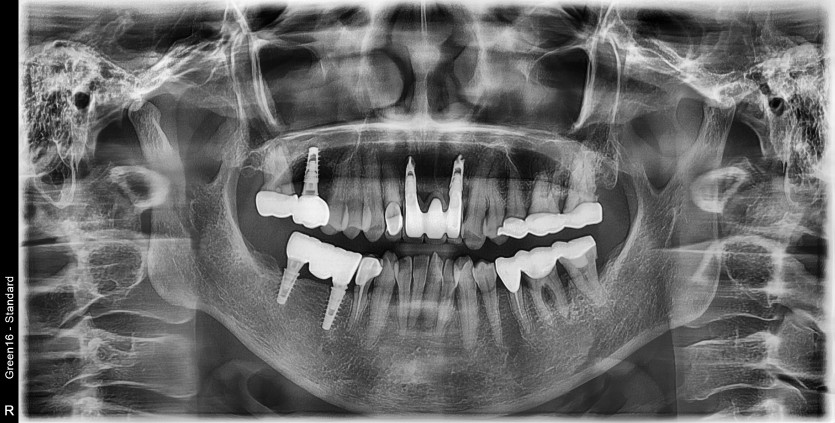

#11.22 타원 임플란트 제거 후

임플란트 재 수술 + 치조골 이식술 시행하였습니다.